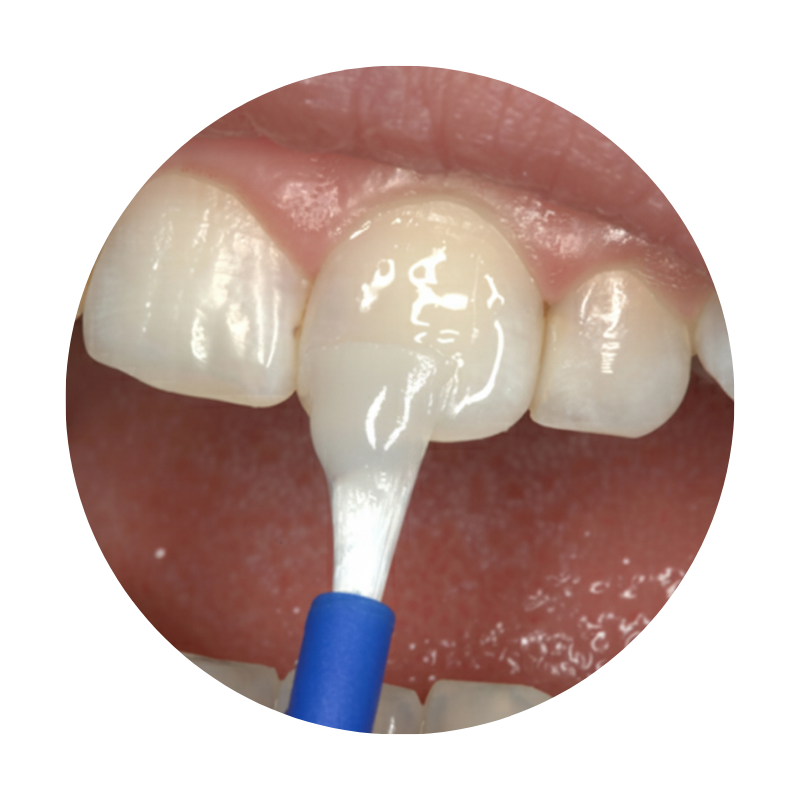

Dental sealants in kids for protection against cavities

Dental Salants

Dental Sealants are thin, flowable fillings applied to the chewing surfaces of back teeth to prevent cavities. They block food and bacteria from settling into deep grooves where brushing can’t reach easily.

The application is quick, painless, and ideal for children prone to cavities. Sealants act as a long-lasting shield, keeping teeth healthier for years.